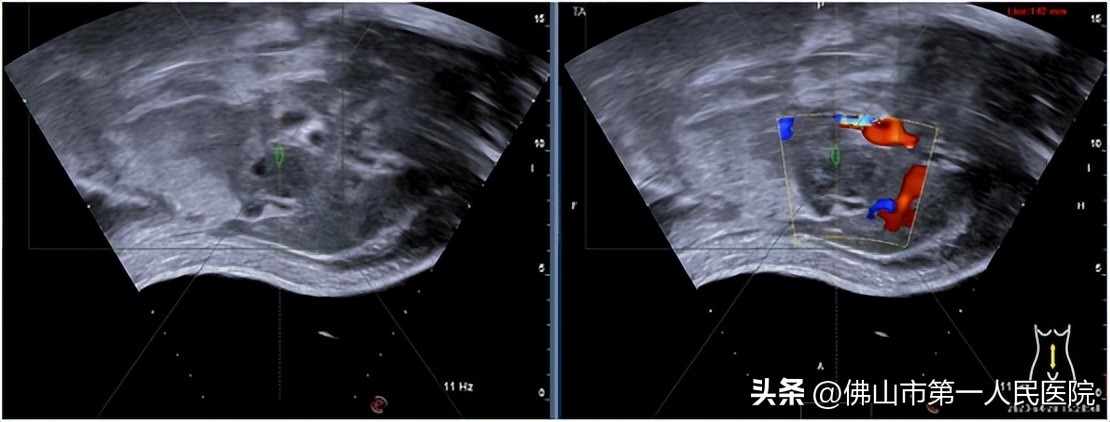

术前超声定位

4月28日,在我院胆胰医学中心苏树英主任及海扶微无创中心梁栋主任组织下,王川博士为患者实施了胰腺癌海扶刀治疗。治疗非常顺利,历时1个小时,按照肿瘤直径做好治疗计划,先病灶中心层面,再依次向病灶边缘延续的顺序给予依次点状消融,定时检测治疗区皮肤,大部分病灶明显可见团块灰度增加,提示病灶已凝固性坏死。患者生命体征平稳,皮肤完好,术后无不适,对治疗效果非常满意。